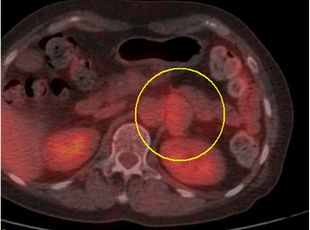

超音波検査、CT検査で副腎腫瘍を認めた場合、血液検査・尿検査などでホルモンを過剰に産生していないかを調べます。

必要に応じてMRI検査や血管造影検査(左右の副腎静脈からホルモンサンプリング)を追加して総合的に診断します。